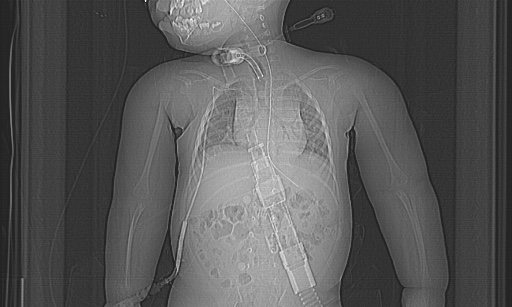

• (生前の頭部CT)位置決め画像で軟部組織の腫大が目立つ。気切されており気管透亮像が目立つ。 肺には大きな無気肺なし。CV は右鎖骨下から挿入。胃管は胃内まで到達。デバイス類に 位置異常なし。 咽頭レベルでは内腔の描出はごく狭いが、声門下から気切部、気管では内腔の狭窄なし。 舌の濃度が低下しており、denervation の状態にあると思われる。 咬筋や胸鎖乳突筋も萎縮している。 軟部組織の腫大は浮腫よりは脂肪組織の増生によるものに見える。

• 年齢から考えると胸郭が過度に扁平化しており、仰臥位での臥床生活の時間が長かったことを示す。頚部気管は右腕頭動脈との交差部で圧迫変形しているが、内腔の狭小化はごく軽度。

• 気切状態。肺全体としては体全体に対する体積が小さいが、気管・気管支内腔は大きい。 生前に自発呼吸がなく、換気不全が持続していたため、陽圧呼吸下で気道の内腔を大きく拡げる管理がされていたことに合致する。

• 胸腺は大きめに見える。年齢からの平均的体積ではおそらく平均的なレベルだが、この様な、重篤な脳障害で臥床生活をしている児としては大きく見える。ただし何か意義のある所見なのかどうかは不明。